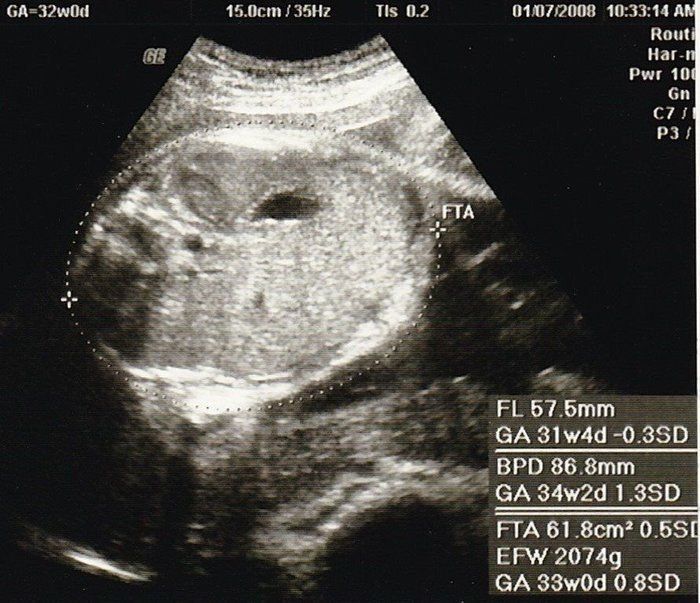

セイコさんの妊娠32週目のエコー写真 少し血圧が高く、浮腫も出てしまう

今日で東京のお医者様の健診は最後です。最後の最後で、血圧がやや高めなことと、少し浮腫みが出てしまって心配をかけてしまいました。娘は順調で、立派な太ももの骨を見せてもらいました。